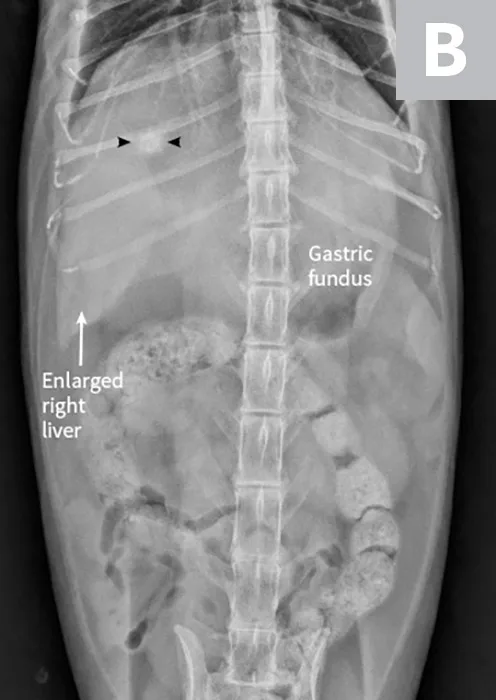

Lateral radiographs of a clinically normal cat (A) and a 14-year-old neutered male domestic shorthair cat (B) presented with icterus and elevated liver enzymes. A normal feline liver should have a sharp, pointed margin (A; arrows) and should not extend past the costal arch; the gastric axis should be parallel to the ribs (A; line). The liver in the icteric cat extends past the costal arch, and has rounded borders (B; arrows). The stomach is displaced caudally (B; line; gastric axis from the fundus to the antrum). An ovoid mineralization (B; arrowheads) is also superimposed with the cranioventral liver in the location of the gallbladder. This cat was diagnosed with cholangitis, lipidosis, and a cholelith.